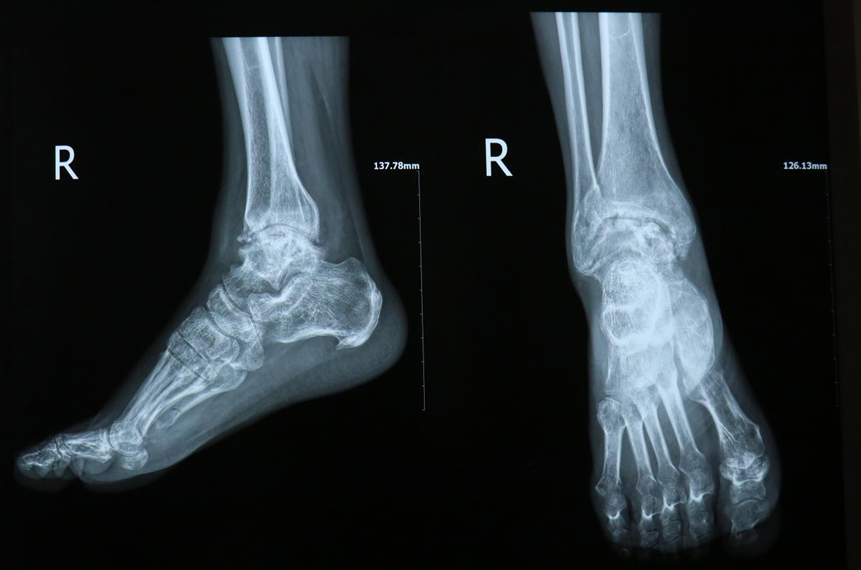

一场意外,轰鸣的机器将她的头皮及颈部皮肤撕扯开来,原本贴在脸颊的左耳孤零零躺在了机器旁;一次“冒险”,医生将离断的耳朵通过吻合直径0.2到0.3毫米的血管寄养到了她的脚背上;后来,她带着脚背上的耳朵生活,每天醒来先查看耳朵的情况,穿宽松的鞋子、走路要放慢脚步;5个月后,这只寄养在脚背上的耳朵终于回到了它本该在的位置……意外突袭一场撕裂的生死考验看着镜中逐渐恢复的容貌,孙女士(化姓)心里满是感激。今年4月,她像往常一样在车间工作,机器运转的轰鸣声中,一场突如其来的意外毫无征兆地降临——高速运转的设备瞬间将她的头皮、面部及颈部皮肤撕扯开来、急救人员赶到时,眼前的景象令人揪心:孙女士的头皮呈螺旋样条